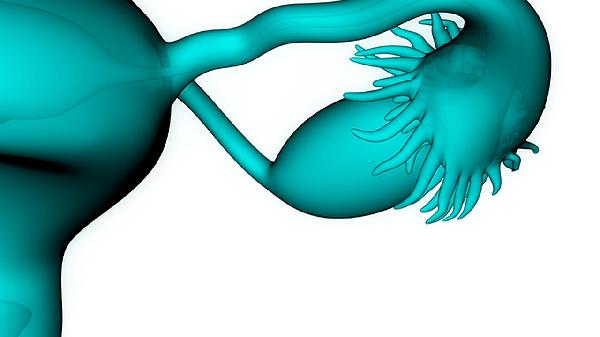

生产过程中由于孩子体型确实比较大,过程非常艰难,为了母子两个的安全医生只能采取了侧切的方式,尽管如此下体还是出现了撕裂的情况,可见生产过程的艰难。

顺产经历过侧切的女性不在少数,相信每个人的心中都有同一个方面的焦虑,就是担心侧切会对以后的生活造成影响,在面对老婆顺产侧切后丈夫究竟是保持何种态度时,一位男士给出了两个不同的答案。

但女性顺产侧切后的关注点不应该着重于在这上面,更重要的是产后要如何护理才能够让身体更快地恢复。

对于侧切的产妇来说一定要注意伤口地清洁消毒,不要发生感染等情况,否则后续承受的痛苦要更大。

对于顺产侧切其实大家也不要过于害怕,并不是每个人都需要侧切才能够顺利生产,而且侧切以后医生会对伤口做非常认真的处理,后续恢复好后是没有太大影响的。丈夫也应该对产妇多一些照顾和心疼,多开导她们帮助打开心结,毕竟妻子刚刚从鬼门关上走了一遭,身体不适的同时不要再让她们承受心理上的不适。